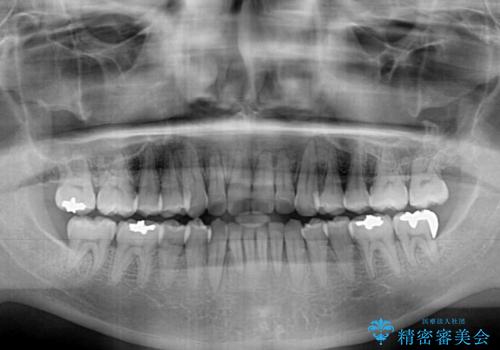

前歯のデコボコ ワイヤー装置での短期間治療

- 1年3ヶ月

治療開始の頃は、食事や歯磨きが慣れず、装置が頻繁に脱落しましたが、2,3ヶ月ほどで慣れ、その後は1年ほどで治療を終えることができました。